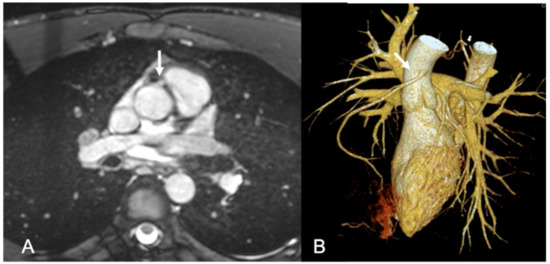

1.1. Computed Tomography and Magnetic Resonance Imaging Benefits

1.2. Role of Coronary CT